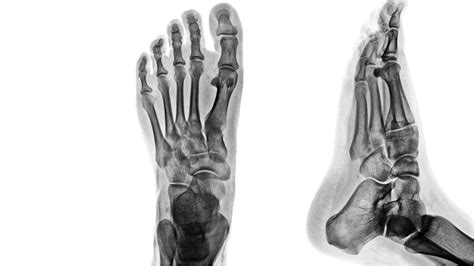

While almost any joint can be affected by Post Traumatic Arthritis, it is most common in weight-bearing joints like the knees, ankles, and hips. The trauma that triggers this condition can range from microscopic damage to severe fractures. Common scenarios include:

Diagnosing Post Traumatic Arthritis usually involves a combination of clinical history and imaging. A physician will review your history of past injuries and order X-rays to check for joint space narrowing or bone spurs. In more complex cases, an MRI may be requested to visualize the soft tissues and determine the extent of current cartilage damage.